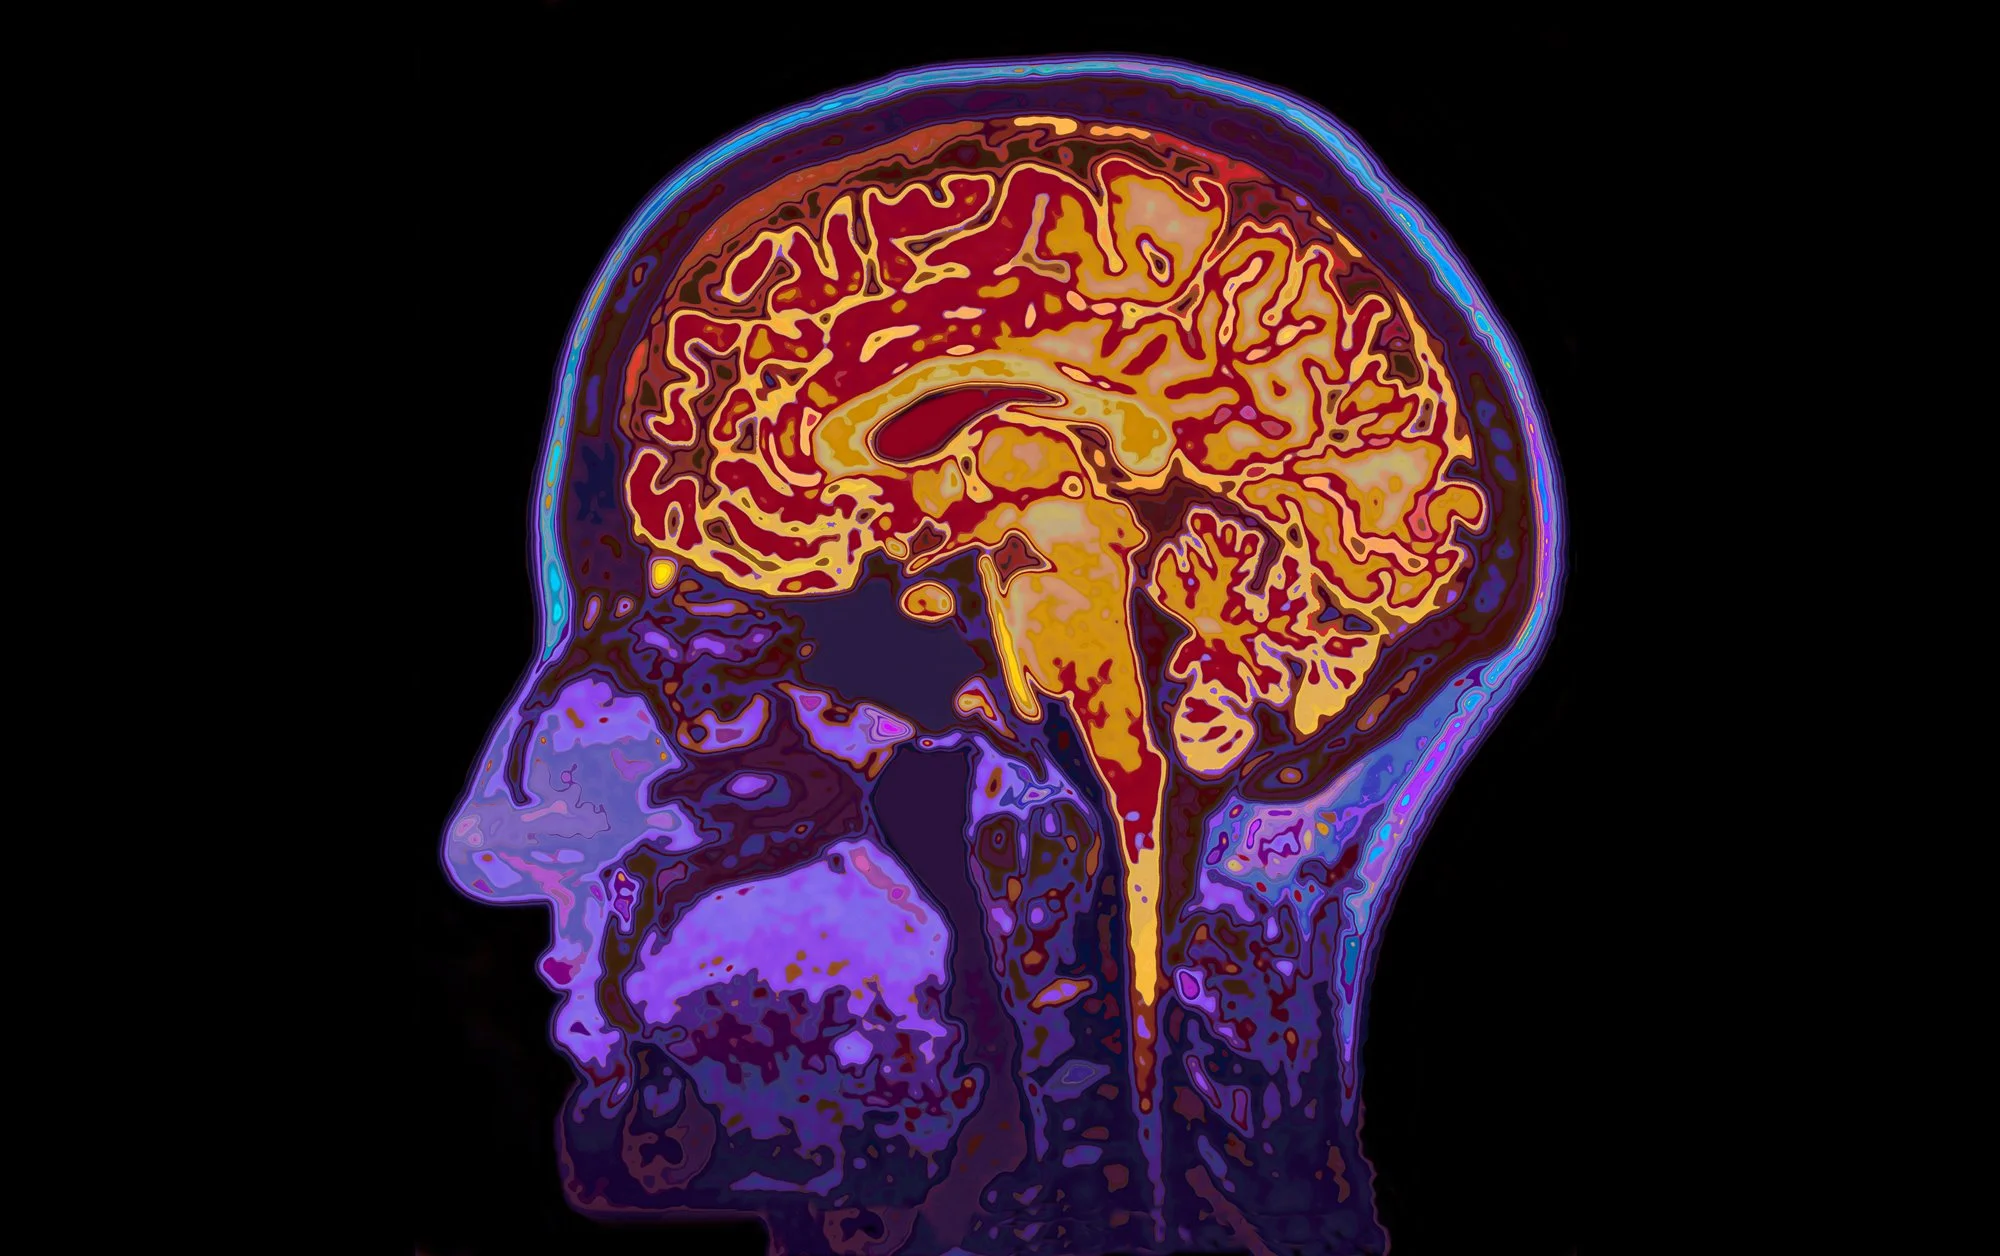

Multiple neurobiological processes are thought to contribute to major depressive disorder. The brains of people who have this condition have been shown to have lower cortical thickness and cell density in the prefrontal cortex, reduced hippocampus volume, and changes to synapse structure and function.58